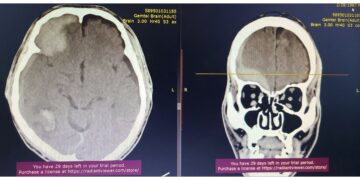

Хан-Уул дүүргийн эмнэлэг тархины хавдар авах мэс заслыг анх удаа хийлээ

Тавдугаар сарын 24-ний өдөр Хан-Уул дүүргийн нэгдсэн эмнэлгийн Мэдрэлийн тасагт хэвтэн эмчлүүлж байсан үйлчлүүлэгчийн СТ оношилгоогоор тархины хавдар оношлогджээ. Яаралтай...